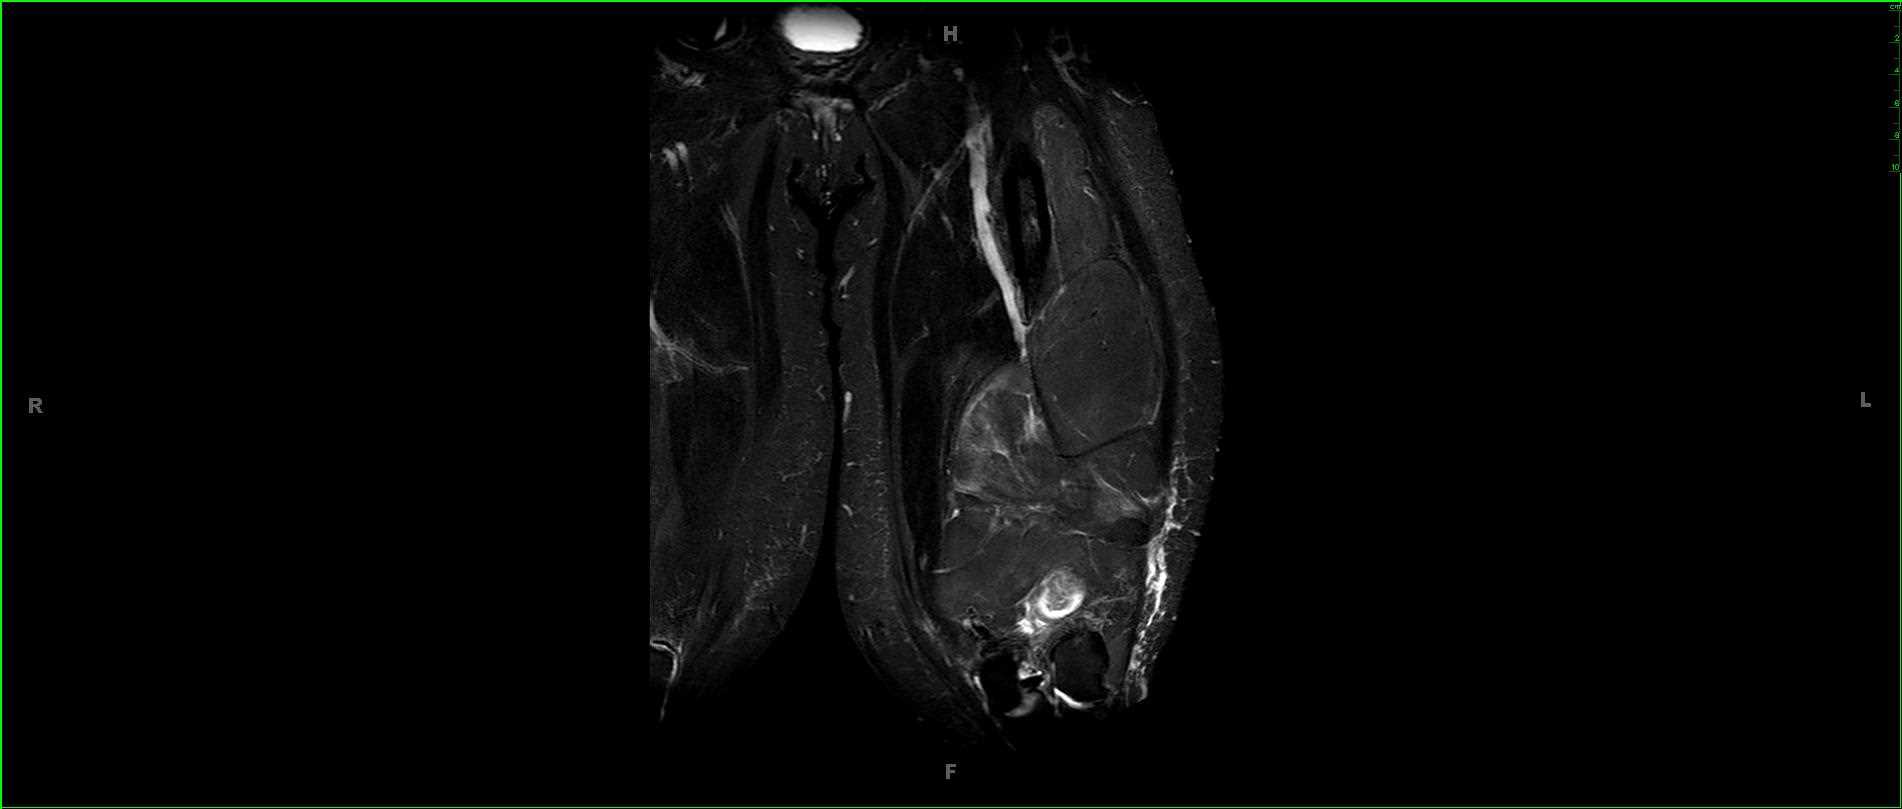

42-year-old male with gradually enlarging left thigh mass. Images demonstrate a multiseptated T1 hyperintense, STIR hypointense, heterogeneously enhancing mass enveloping the left femoral diaphysis and extending into the surrounding soft tissues. No periosteal reaction. There are enhancing, wispy, septations on the postcontrast images with more nodular excrescences at the inferior most aspect of the mass. On resection, this lesion was found to be a well-differentiated liposarcoma, which represents the second most common soft tissue sarcoma. Liposarcoma typically arise in adults between the ages of the 40 and 60 years. Typical locations include the extremities or retroperitoneum. Well-differentiated liposarcoma is the most common subtype, occurring in greater than 50% of cases. Extremity liposarcomas are typically slow growing and have variable rates of localized disease recurrence with deeper lesions more likely to recur. Primary surgical treatment is with wide local excision.